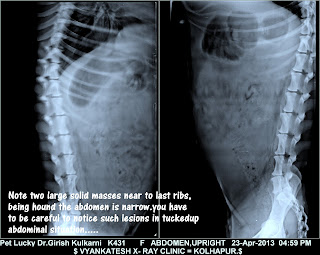

Depending upon the tissue of origin the

clinical symptoms of ovarian tumour vary. Main clinical symptom of epithelial

cell tumours is malignant ascites. Germ cell tumours are associated with

hormonal dysfunction and space occupying mass in abdomen. Routine abdominal

radiographs show enlarged mass with calcified foci. Stromal tumours secrete